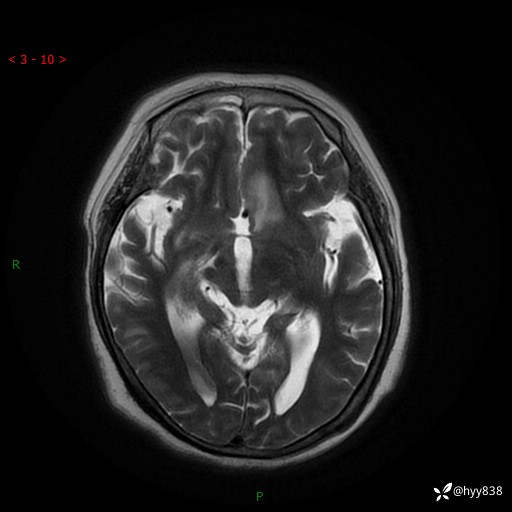

患者性别:女

患者年龄:57岁

简要病史:昏迷入院

颅脑MRI(T2WI+DWI)